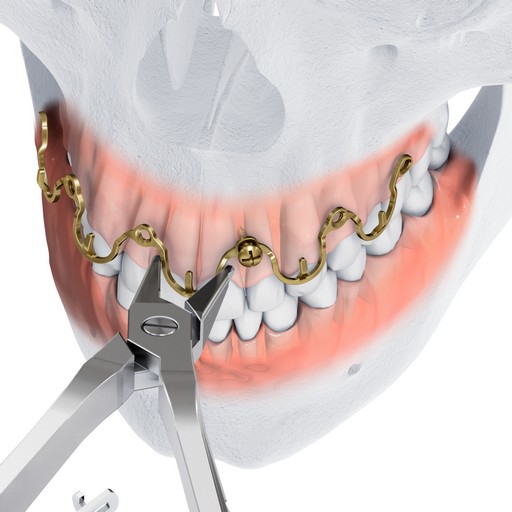

MatrixWAVE MMF (Figs 1-8) is a novel bone-borne MMF system that combines the strength and rigidity of arch bars with the speed and simplicity of IMF screws. It consists of a wave shaped plate that is attached to the mandible and maxilla with self-drilling locking screws (Fig 3). The plate is adaptable and can be extended horizontally (Fig 4) to allow screw hole placement in the optimal location to avoid tooth roots and nerves. The locking mechanism avoids compression and ischemia by keeping the plate away from the mucosal tissues.

The dental arches are brought into occlusion by wiring around the plate hooks and/or accessible screw heads. The self-drilling locking screws sit proud to the plate. This minimizes soft tissue growth over the screw, and provides additional anchor points for optional bridle wires. Upon insertion, screws can be angled at up to 15 to aid in posterior fixation and to optimize dental occlusion.

Maxillomandibular fixation can be achieved more quickly using the Matrix WAVE plate than by using arch bars. Removal is simple, and can be done in a non-OR setting. The MatrixWAVE plate design eliminates the need for circumdental wiring. This has several advantages, including reduced risk of needle stick-like injuries and reduced risk of tooth loosening. Additionally, the MatrixWAVE MMF system covers less tooth surface, allowing more access to the teeth for cleaning. The design of the plate maximizes patient comfort, as it has rounded, smooth edges. The screw heads are also rounded, and the plate hooks can be bent towards the gingiva after wiring.

The MatrixWAVE plate was attached to the maxilla with screw placement in the inter-root spaces (Fig 2). A second MatrixWAVE plate was attached in corresponding position to the mandible, with screw placement in the inter-root spaces (Fig 3). Wires were placed around the plate hooks to bring the dental arches into occlusion. Note the preexisting anterior open bite (Fig 4). Careful adjustment of the MatrixWAVE plate and wiring in the region of the mandibular fracture allowed the bone fragments to be precisely aligned without the requirement for screw repositioning (Fig 5). The postoperative panoramic x-ray (Fig 6) shows the two MatrixWAVE plates in situ, with other plates used to fixate the left mandibular angle fracture. Note that a portion of the Matrix- WAVE plate was removed from the left molar region in the mandible (Fig 6).